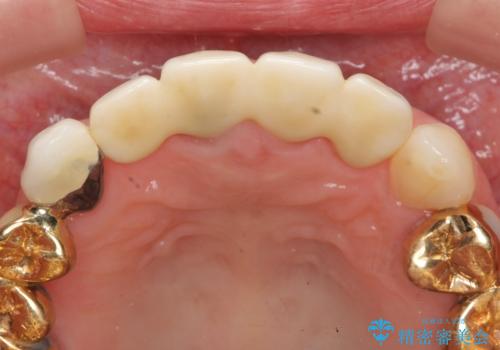

即切歯の抜歯を行う場合犬歯を含めたブリッジによる補綴計画を立てることが多いですが、今回は犬歯から大臼歯にかかる大きなブリッジが既に装着されていたため予算とご希望を相談し前歯のみの延長ブリッジ補綴で治療を行っていくこととしました。

- 54万円(仮歯・感染根管治療・ファイバーコア・ジルコニアクラウン×4) (税別)費用は治療当時の料金となります

歯列全体を治療の対象とする治療計画が予算や期間により難しい場合、状況に応じて最善の治療結果が出せるよう治療のゴールを相談しながら決定することが可能です。